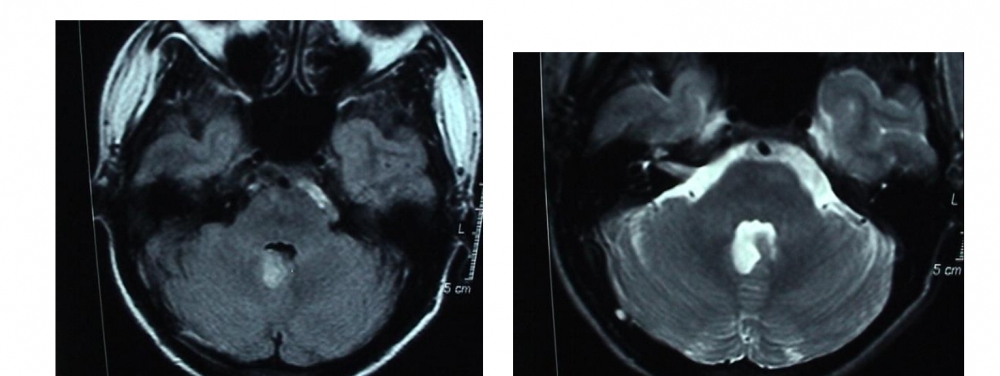

This arises from lesions of the nodulus (Video 2 below). Downbeat nystagmus may increase, suppresss or convert to upbeat nystagmus when adopting a supine or prone head position1.

This arises from lesions of the posterior cerebellar vermis. There are frequently other associated eye signs, such as saccadic pursuit and gaze-evoked nystagmus.